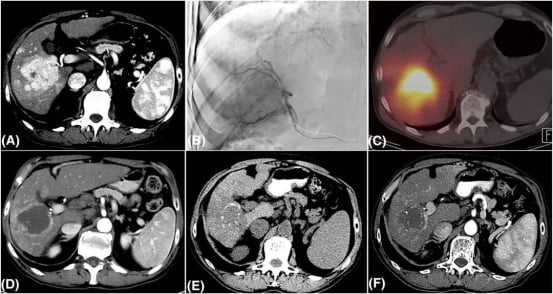

图1 一例接受选择性钇90治疗的HCC患者在2年随访中维持CR

近期多项国际研究都强有力地支持了TARE在经过严格筛选的早期肝细胞癌(HCC)患者中的卓越疗效。例如,一项回顾性名为LEGACY的研究对162例诊断为单发性、直径小于8厘米的HCC患者进行了TARE治疗。结果显示,这些患者的“客观缓解率”(Objective Response Rate, ORR,指肿瘤缩小达到一定程度的患者比例,通常包括完全缓解和部分缓解)高达88%,这是一个非常令人鼓舞的数字。患者的“中位缓解持续时间”(Duration of Response, DOR,指从达到缓解到肿瘤再次进展的时间)为11.8个月,而2年“局部无进展生存率”(Local Progression-Free Survival,指局部肿瘤没有进展的比例)更是高达93.9%。这些数据清晰地表明了TARE在精准控制和清除局部肿瘤方面的强大能力。

另一项前瞻性研究报道,对于肿瘤数量不超过3个的HCC患者,TARE治疗后6个月的客观缓解率达到81%,且中位缓解持续时间更是长达惊人的32.7个月。这些数据都强有力地证明了TARE的长期肿瘤控制能力和持久疗效。

更令人振奋的是,多中心前瞻性Doorway研究根据独立的专家中心审查,得出的“最佳客观缓解率”(BORR)高达98.5%,这意味着几乎所有可评估的患者都达到了肿瘤缓解!该研究实现了100%的局部肿瘤控制率,患者的“缓解持续时间”(DOR)中位数超过300天。同时,TARE在安全性方面表现良好,患者的耐受性高,治疗过程中的不良反应可控。